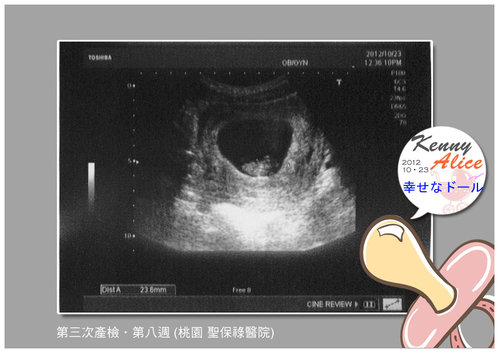

===== 小B寶在哪裡呀?? 媽咪都看不到你 =====

我的小B寶你在哪裡呀?! 快出來讓媽咪看看你......該見客囉!!